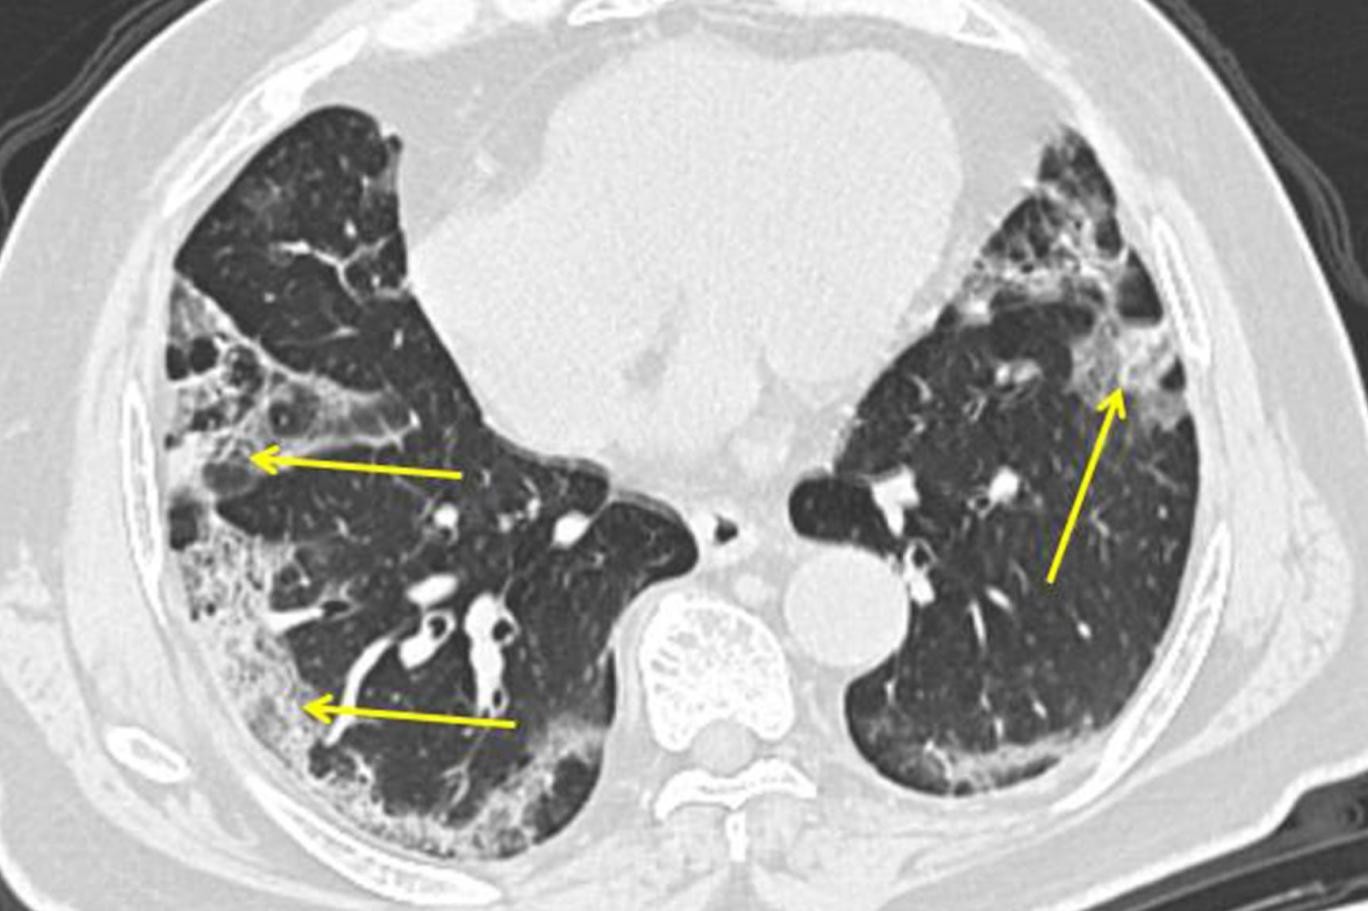

телефон кт легких (100) фото